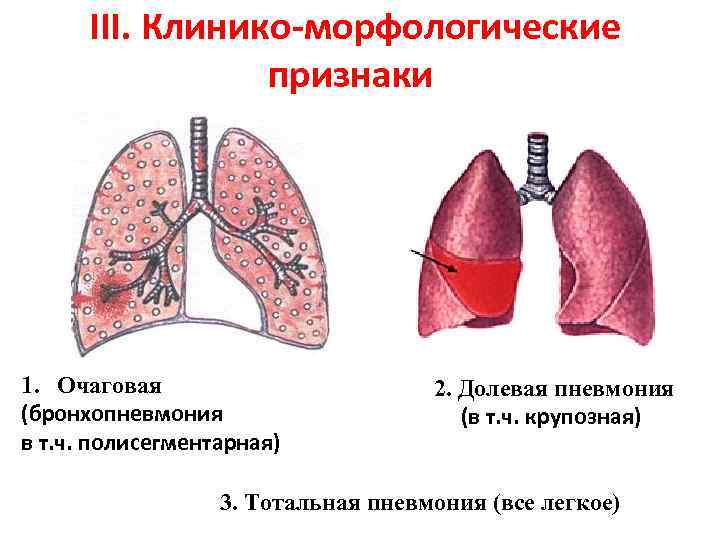

Медицинская тема: легочные осложнения при пневмонии